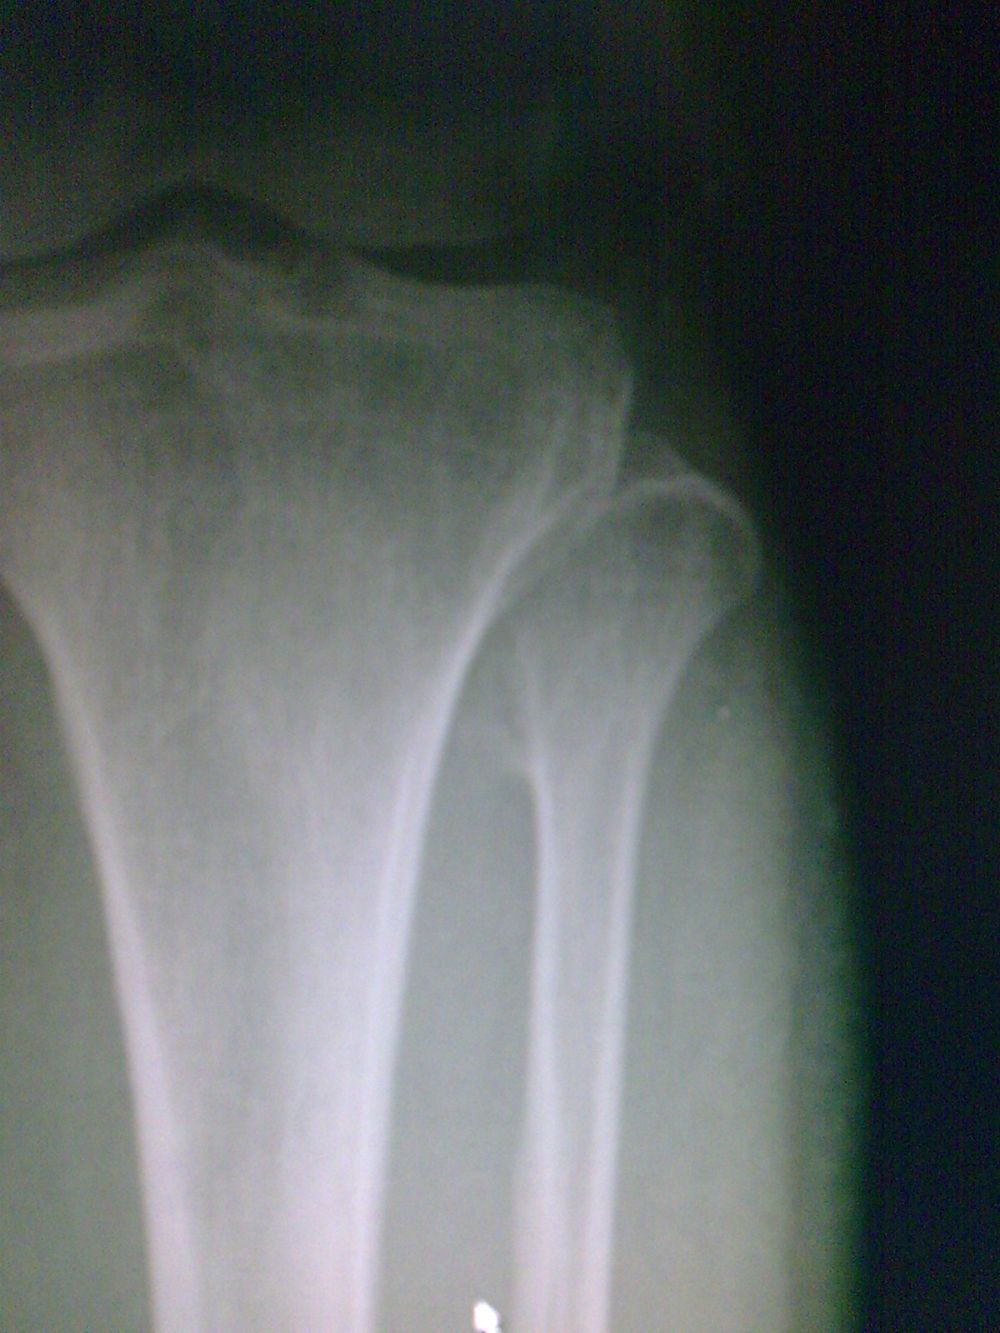

标题: CT19437:男性,四十岁,因外伤入院,X光平片发现腓骨近端 [打印本页]

标题: CT19437:男性,四十岁,因外伤入院,X光平片发现腓骨近端

建议除外骨肿瘤【典型骨肉瘤ct表现。1局部骨破坏,2骨膜反应,3周围软组织肿块;4,与骨膜肉瘤难区别】

kaolv 骨软骨瘤

支持考虑骨软骨瘤

考虑腓骨上端骨软骨瘤。

符合骨软骨瘤表现!

首先考虑比目鱼肌牵曳征,其次考虑骨软骨瘤。